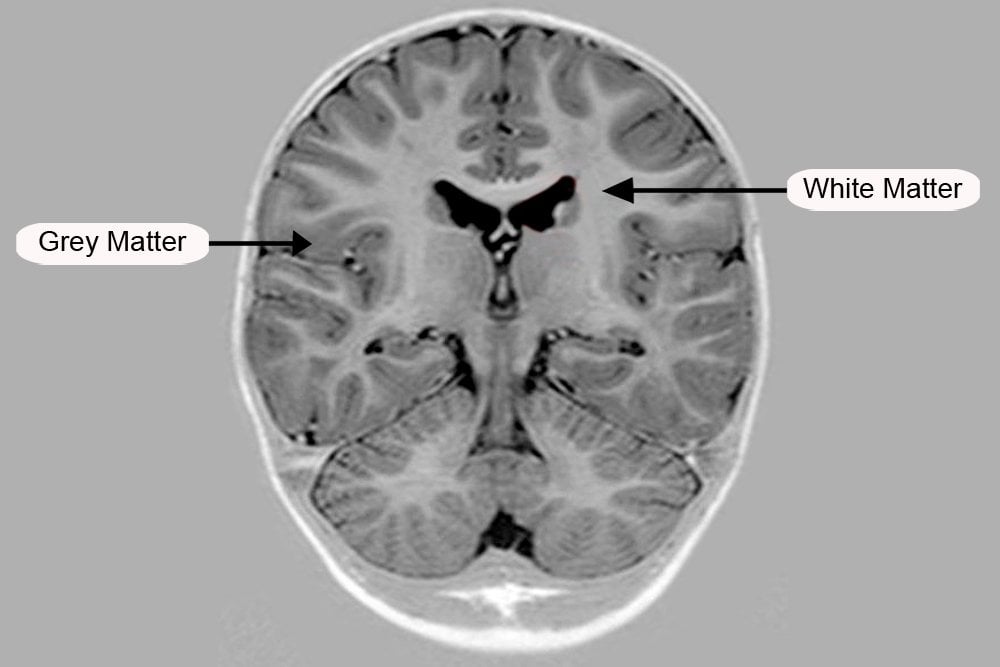

Grey And White Matter Of The Cerebrum

The cerebrum is divided into two parts, the outer grey matter covering the surface of the cerebrum called the cerebral cortex and the inner medullary region called the white matter.

The cerebral cortex which comes from the Latin word for bark is covered by a layer that is approximately 1/10th of an inch thick. This layer contains grooves and ridges, which increase the surface area of the cortex. There are about 20 billion neurons and over 300 trillion synapses in the cortex alone. An increased amount of surface area, therefore, allows for more neurons to be present.

One must have heard the term “grey cells” before, especially fans of Hercule Poirot. The fictional detective often referred to them as his, “little grey friends”. These refer to the cells in the cerebral cortex where the many neurons lack myelin sheath covering. The myelin sheath is a fatty covering around the axons of cells which give a whitish appearance to the inner medullary regions of the cerebrum.